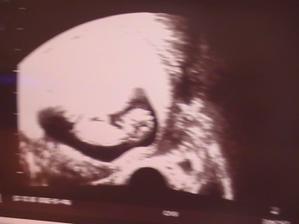

11tt - náš malý zázrak🙂